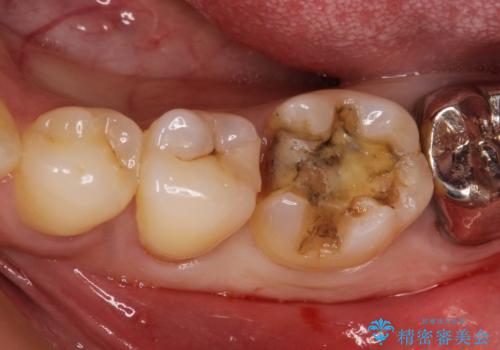

[ セラミック治療 ]目立つ奥歯の銀歯を白くする

![[ セラミック治療 ]目立つ奥歯の銀歯を白くするの症例 治療前](https://seimitsushinbi.jp/wp/wp-content/uploads/2021/11/200905b82e48a56c05450d91be582e11-1-500x350.jpg?v=1637229926)